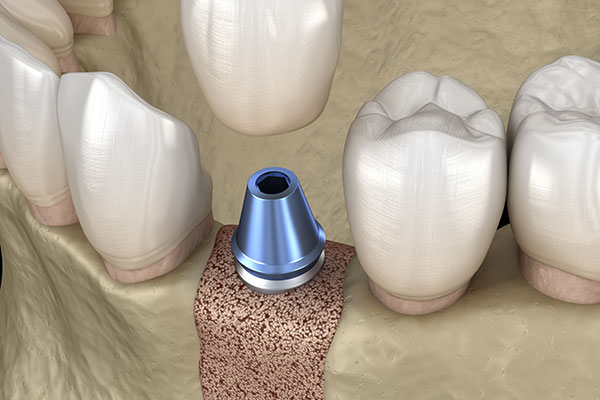

インプラント治療は、インプラントを埋め込む位置にしっかり骨がある必要があるため、骨の状態によって治療ができないと診断されることがありますが、当院は、骨を補う治療方法を行うことができるので、このようなケースでも治療の可能性が検討できます。

骨の厚みが不足している場合にはGBR、上あごの骨に高さが足りない場合にはソケットリフトという手法を併用し、インプラントを埋入するために必要な骨量を確保します。難しい症例でも可能な限り治療ができるよう努めます。是非一度ご相談ください。

アバットメントの取り付け

インプラントがしっかりと骨に結合した後、人工歯を支えるためのアバットメント(人工歯の土台)をインプラントに取り付けます。この手術も局所麻酔で行い、比較的短時間で終了します。